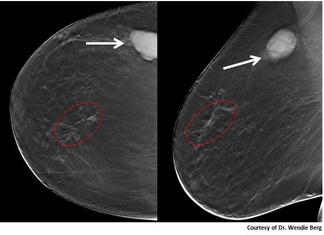

The 3-D breast tomosynthesis is a special type of mammogram that produces a 3-dimensional image of the breast by using several low dose x-rays obtained at different angles, with multiple thin-section images of the breast. 3-D breast tomosynthesis technology has several advantages and disadvantages.